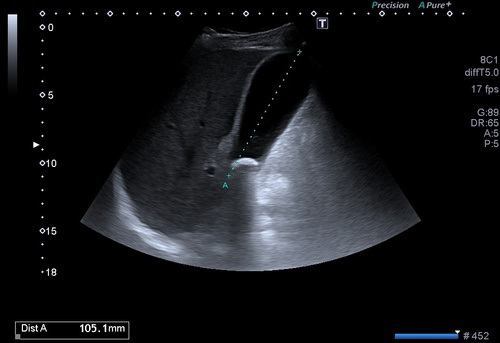

Batın ultrasonogafisi ile karaciğer, böbrekler, böbrek üstü bezleri, pankreas, safra kesesi, mesane, rahim, yumurtalıklar, prostat gibi belli başlı organlar değerlendirilir. Ayrıca bu organlar dışında batın içerisindeki sindirim sistemi organlarının ( mide, on iki parmak barsağı, ince ve kalın barsaklar) özellikle duvar yapıları ve önemli damarsal yapılar da değerlendirilir.

Batın ultrasonu ile karaciğer içerisindeki bir kist ya da kitlenin, karaciğerin yaygın hastalıklarının (hepatit, siroz vb.), karaciğer içerisindeki damar ya da safra yollarının hastalıklarının tanısı konulabilir. Safra kesesi taşları, safra çamuru, safra kesesi polipleri, safra yolları taşları ve safra kesesi duvarı kökenli kitleler ultrason incelemesinde görüntülenebilir.

Böbreklerin kist ya da kitleleri, böbrek taşları, böbrek kanallarında genişleme ve tıkanıklık, ciddi böbrek enfeksiyonları (pyelonefrit), böbrek üstü bezlerinin kitleleri ya da kalınlaşmaları, pankreasın enfeksiyonları, kist ya da kitleleri, pankreas kanalı tıkanıklıkları, mesane duvarı kitleleri, divertikülleri, mesane duvar enfeksiyonları(sistit), mesane taşları, rahim duvarından köken alan myomlar, rahimin içerisinden kaynaklanan kitleler, rahim kanalı hastalıkları, yumurtalıkların kist ya da kitleleri, içerisindeki follikül sayıları, endometrioma gibi kanamalı kitleler, prostat büyümesi, kitleleri gibi birçok hastalık batın ultrasonu ile değerlendirilir.

Batın içerisindeki mide ve barsakların duvar yapılarından kaynaklanan kitleler, barsak tıkanıklıkları, çocuklarda invajinasyon adı verilen barsakların iç içe geçmesi, apandisit, divertikülit, crohn gibi hastalıklar, batın içerisindeki ana damarların tıkanıklıkları ya da genişlemeleri, batın içerisindeki sıvı artışı ve kanama da bu yöntemle değerlendirilir.

Batın duvarını oluşturan kas tabakasındaki patolojiler ( göbek fıtıtğı, kasık fıtığı, kitleler, abseler vb.) batın ultrasonu ile değerlendirilir.

Ayrıca travma hastalarında, ana organlardaki yaralanmalar, batın içi kanama yada mide barsak sistemi yaralanmalarına bağlı batın içi havanın değerlendirilmesinde batın ultrasonu ilk tercihtir.